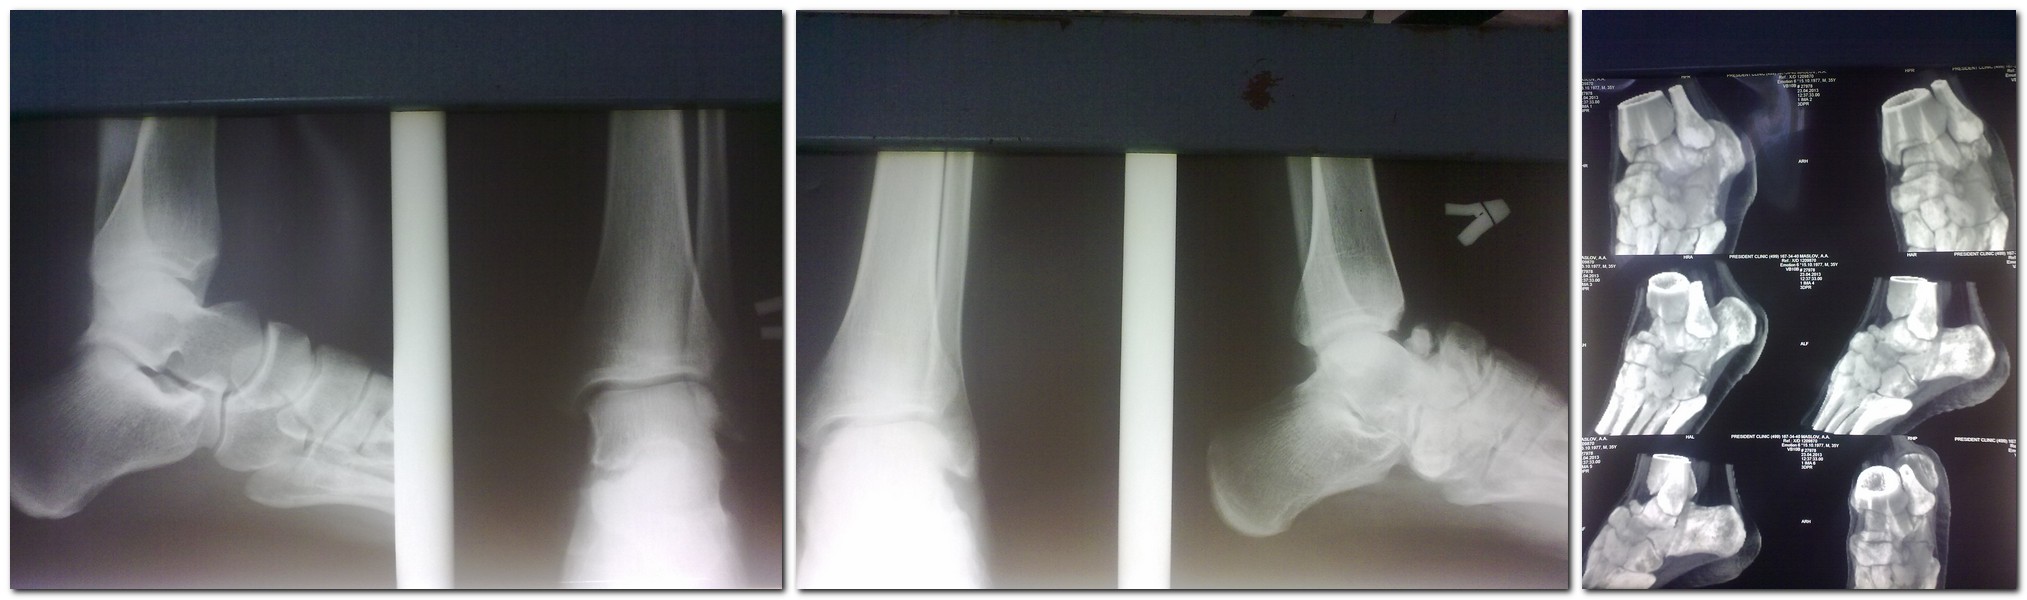

Доброго времени суток, дорогие коллеги. Представляю Вашему вниманию своего знакомого. Парень 35 лет получил травму 20 лет назад при падении с высоты.

Первая помощь оказана в одной районной больнице, отболело и забыл... Но 6 месяцев назад пришлось вспомнить; постепенно начали беспокоить боли в области сустава Шопара после продолжительной нагрузки, периодически употребляет НПВС (2 раза в неделю). Итак вопрос: кто может помочь бедолаге? И у кого есть какие идеи решения данного вопроса. Всем спасибо!

Артродез таранно-ладьевидного сустава а для верности всего Шопара.